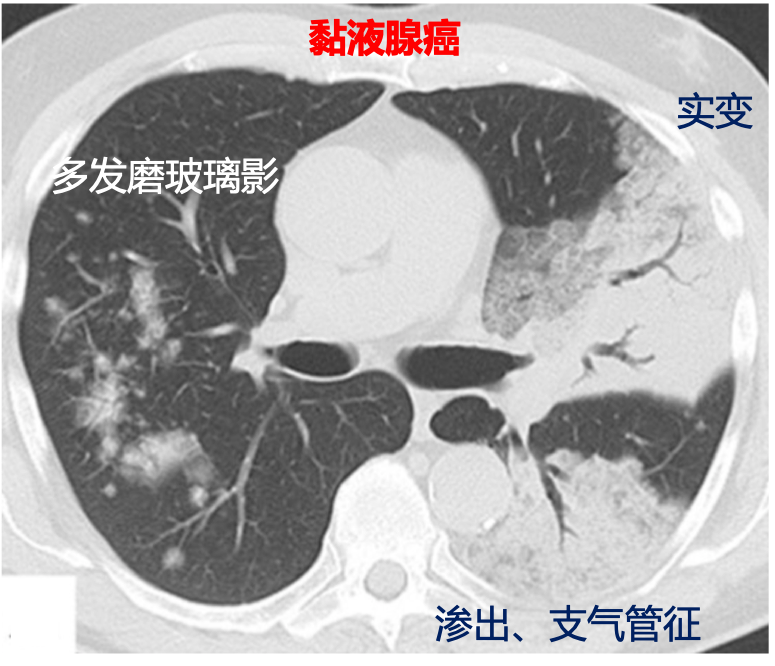

影像学表现

先正名,“黏液”还是“粘液”? 子曰:名不正则言不顺,言不顺则事不成。写这篇文章前,我也经常将“黏”“粘”混用,但既然要写文章,那就要搞清楚两字的区别。 百度上说1988年《通用规范汉字表》中二者都是规范字,但却拥有不同的词义:“黏”作为形容词,形容物体具有黏稠的特性,发音为“nián”;而“粘”则作为动词,指把不同的物体胶合在一起的动作,发音为“zhān”,只有在作为姓氏时,才发“nián”音。我院早年病理报告两个字混用,近2年均用“黏液”。因此,本文标准的写法是“黏液腺癌”,其它带黏液的疾病有心房黏液瘤、卵巢黏液性囊腺瘤/癌等。 当然,在医疗常规应用中,两个字基本上是互通的,“粘”更好写一点,可能应用范围更广。只是希望大家在写论文、毕业答辩时,能更规范、更严谨一些。 黏液腺癌可能来源于具有分泌功能的杯状细胞、柱状细胞。从WHO腺癌分类表中可以看到,原位腺癌(AIS)到浸润性腺癌,都有可能伴黏液分泌,而只有在浸润性腺癌中才有黏液腺癌这个名称(其为浸润性腺癌的一个变异型)。“分泌黏液的腺癌”与黏液腺癌的区别主要有:前者分泌黏液细胞数量少、占比低,后者可分泌黏液的癌细胞占比高,肿瘤细胞呈杯状或柱状是特点,免疫组化TTF-1通常为阴性。黏液腺癌也可以像普通腺癌一样呈现贴壁、腺泡、乳头、微乳头样生长。 黏液腺癌一般分化较好。癌细胞内富含黏液,肺泡内亦充满黏液,缺少促进结缔组织增生的纤维化区。因此,从大体上看瘤体组织呈半透明、胶冻样,非常柔软、易碎。肿瘤细胞可随黏液在气腔内播散,导致影像学上多发的肺炎式表现。 黏液腺癌发生与KRAS(G-A)点突变有关,因此KRAS突变率非常高(70~90%),相反EGFR基因突变概率非常低(<3%)。另外需要指出的是,实体型为主伴黏液分泌的浸润性腺癌,ALK融合概率较高(35%)。 2015WHO肺腺癌分类标准 黄承路, 韩少辉, 徐苏琴. 原发性肺黏液腺癌的研究进展[J]. 实用肿瘤学杂志, 2017:5(31),463-467. WD Travis, E Brambilla, M Noguchi, et al. IASLC/ATS/ERS International Multidisciplinary Classification of Lung Adenocarcinoma[J]. J Thorac Oncol, 2011, 6(2):244-285. 王恩华,张杰. 临床病理诊断与鉴别诊断-气管肺胸膜及纵隔疾病[M]. 北京: 人民卫生出版社, 2018: 103. 黏液腺癌以分泌黏液为特点,因此CT上以单发或多发磨玻璃病变、大片渗出、肺实变、空洞、支气管征为主要表现,纵隔淋巴结肿大少见。 黏液腺癌容易与肺炎、肺结核等良性疾病混淆。通常刚刚发现时会进行抗感染或抗结核治疗,若保守治疗无效需想到黏液腺癌可能。对于不规则的小片状磨玻璃影,即使第一诊断没想到肺癌,也需要定期复查,不可大意。 早期黏液腺癌影像学表现类似于当今流行的新冠肺炎(COVID-19),需要仔细检查,以免漏诊、误诊。 更多CT图片将在后面典型病例中展示。 黏液腺癌与新冠肺炎很相似 早期黏液腺癌患者可无明显症状,当肺部出现大片磨玻璃影、渗出、肺实变时,可有咳嗽、咳痰症状。细菌性肺炎常见的发热、白细胞升高症状不多见。患者症状通常与肺部表现不一致(CT上看病情较重,但症状不重)。 与其它肺癌一样,以手术治疗为主。但因为CT上类似肺炎表现,一般发现后先进行抗感染治疗,如果病灶没有吸收,一定要想到肺癌可能,通过手术或穿刺尽早明确诊断。 1、单发磨玻璃病变、结节型病变,高度怀疑肺癌的,一般直接手术切除。 2、多发磨玻璃病变,明显渗出,大片肺实变者,若病变局限在一个肺叶可手术切除,若病变弥漫多个肺叶,可CT引导下穿刺明确诊断后行化疗、靶向或免疫治疗。 通过查阅文献,黏液腺癌又分为孤立结节型和肺炎型。孤立结节型黏液腺癌预后较好,5年无疾病生存率(DFS)可达65~84%,5年生存率(OS)可达86%。肺炎型黏液腺癌预后有两项研究差别较大,5年DFS A研究为0,B研究为65%,生存率上,A研究没有5年OS数据,B研究为77%。 我个人的经验是,肺炎型黏液腺癌肿瘤细胞恶性程度不高,但容易在现内浸润生长,在短期内(3个月左右)影像学上就有明显进展。虽然进展迅速,但患者生活质量、生存期影响较小。例如,若是其它类型腺癌,当出现明显双肺转移时,患者一般状态较差,身体消耗症状明显;但肺炎型黏液腺癌双肺转移、多发空洞、实变是常态,患者身体不适症状较轻,日常生活影响小,总生存期可能减少并不明显。因此我更相信肺炎型黏液腺癌5年DFS为0。 A Nie K, Nie W, Zhang YX, et al. Comparing clinicopathological features and prognosis of primary pulmonary invasive mucinous adenocarcinoma based on computed tomography findings[J]. Cancer Imaging, 2019, 19(1). DOI:https://doi.org/10.1186/s40644-019-0236-2 B Lee HY, Cha MJ, Lee KS, et al. Prognosis in Resected Invasive Mucinous Adenocarcinomas of the Lung: Related Factors and Comparison with Resected Nonmucinous Adenocarcinomas[J]. Journal of Thoracic Oncology, 2016, 11(7):1064-1073 DOI:http://dx.doi.org/10.1016/j.jtho.2016.03.011 男性,86岁,2015年5月CT发现右肺下叶占位,当时抗感染治疗后未再复查。 2018年5月复查CT发现右肺下叶完全实变,并伴有肿瘤消耗症状,但不重,完善检查后行胸腔镜右肺下叶切除术。 病理为黏液腺癌,分期为pT4N0M0,IIIA期,KRAS突变阳性。 家属考虑患者年纪较大,无法进行化疗等辅助治疗,故术后未进行复查。患者术后生活质量明显改善,常进行游泳锻炼。2020年3月,患者出现明显刺激性干咳。行胸部CT检查发现双肺多发磨玻璃影、实变、空洞、胸腔积液。考虑肿瘤复发,PD。于2020年4月行特瑞普利单抗免疫治疗。 点评 该患者具有黏液腺癌典型特征: 1、起病时无明显症状,复发后CT上看似乎很重,进展很快,但患者实际生活影响不大,一般状态良好。 2、CT表现为肺实变,复发后表现为双肺渗出、磨玻璃影、空洞。 3、T分期很高,N分期为0。KRAS突变阳性。 4、患者年纪太大,先用免疫单药,最好能加用培美曲塞,一起治疗。 5、患者2年PFS为0,OS可能超过3年。 女性,78岁,2010年体检发现双肺多发磨玻璃病变,抗感染治疗后无明显变化,以后每年复查CT至2015年,期间双肺病变变化不大。 2019年9月至10月以培美曲塞+帕博利珠单抗辅助治疗两周期(外院),11月复查CT,上叶后段及下叶背段病灶范围减小、密度降低,但下叶基底段出现渗出表现。外院考虑间质性肺炎,停免疫化疗,口服强的松治疗肺炎。 2019年12月、2020年3月复查CT,双肺病变持续加重,外院认为间质性肺炎进展,继续强的松治疗。 2020年4月,患者来我院就诊,经过讨论,认为患者两周期免疫治疗和化疗是有效的,停治疗后病变范围增大为肿瘤进展,而非间质性肺炎。因此,让患者逐步停用强的松。以紫杉醇+铂化疗。 1、发现肺部病变,复查要按时、不可中断,该患者前5年肿瘤进展缓慢,但肿瘤生长加速时中断的复查,导致肿瘤直接发展到晚期,失去手术机会。 2、疗效评价要慎重,不能免疫治疗后看到类似“炎性渗出”表现就认为是间质性肺炎,黏液腺癌就是以双肺渗出为典型特征,疗效评价失误就会导致治疗方案南辕北辙。 3、我更倾向于原方案免疫+培美单药化疗,但上级医师认为培美可能作用有限,更换为紫杉。 4、还是要强调外科医生对片子的敏感性。胸外科医生对患者是全方位负责,可以将一种疾病的临床表现、CT影像、病理类型、基因突变、术中情况串联起来。只要用心,不需要太多病例就能抓住一种疾病的主要特征。这也是为什么我的导师王俊院士常说“胸外科医师的阅片水平应该高于放射科、肿瘤科、呼吸科医生”。CT报告更多是一种查漏补缺,帮助我们不要漏掉一些次要病变,但疾病的诊断、治疗方案的选择还是要靠胸外科医生的判断。 8 女性,50岁,体检发现双肺结节入院,无特殊症状。 右肺中叶占位,大小5.6*3.4cm,分叶征明显,内部可见液性密度,边界清,增强不均匀强化。 左肺上叶结节,大小2.2*1.8cm,余特征同上。 2017年9月行胸腔镜右肺中叶切除、淋巴结清扫术,病理黏液腺癌,T3N0,KRAS(G12C)突变阳性。 2018年1月二期行胸腔镜左肺上叶前段切除、淋巴结清扫术。病理黏液腺癌,T1cN0,KRAS(G12C)突变阳性。 术后行四周期培美曲塞+奈达铂化疗。 最近2019年12月复查未见复发。 点评 从影像上看,该患者属于结节型黏液腺癌,没有典型双肺渗出、磨玻璃影表现。双肺病变病理类型、基因突变均相同,淋巴结又是阴性,考虑肿瘤同源、由气腔播散导致。患者术后定期复查未发现进展,预后良好,与多原癌相似。 所以说肿瘤一定要早诊早治,当肺部病变数量有限,可以手术根治性处理时,治疗效果好;当病变在肺内扩散、融合成片时治疗效果就比较差了。 黏液腺癌有独特的影像学表现、病理特征、基因突变、预后转归。 CT上双肺磨玻璃影、渗出、实变、空洞等类肺炎表现是特征。需与肺炎、结核鉴别。孤立结节型黏液腺癌可能是其早期表现,晚期可能通过气腔播散导致双肺弥漫性病变(猜测)。 病理上细胞内外富含黏液、形似柱状细胞杯状细胞是特点,肿瘤细胞可呈贴壁、乳头、微乳头样生长。KRAS突变阳性率高。几乎无淋巴结转移。 早期生长慢,但仍快于一般磨玻璃结节,后期进展迅速,像肺炎一样短期内影像学上就有显著变化。但较重的肿瘤负荷与生活质量下降不呈正比。早期未弥漫开来时切除效果好,复发率低。肿瘤进展后容易复发,但患者生存期仍相对较长。 进展后单纯化疗效果不佳,可考虑联合免疫治疗。来源、病理特点